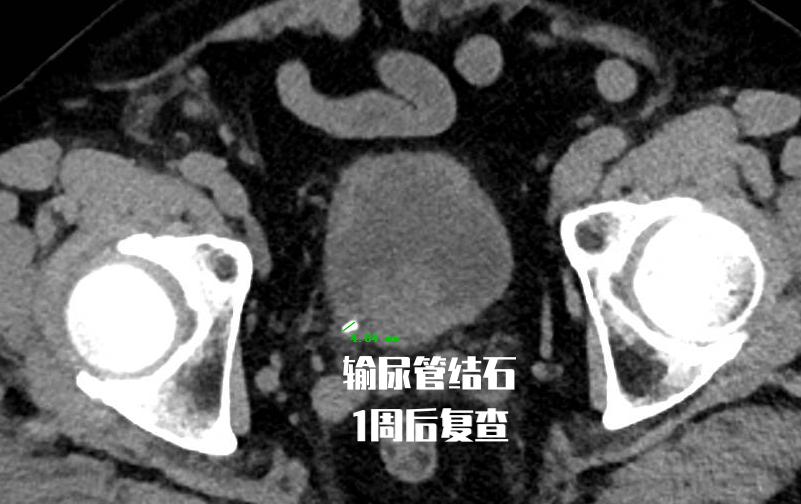

老王今年65岁,1周前因输尿管结石到门诊就诊, 做了CT检查提示结石位于输尿管末端,结石大小5mm。 根据他的结石大小和部位, 选择口服药物保守治疗,并嘱咐患者多饮水和加强活动。 但是1周时间过去了, 老王复诊时的CT提示他的结石仍然没有排出 。于是老王在昨天接受了输尿管镜下钬激光碎石术的治疗。